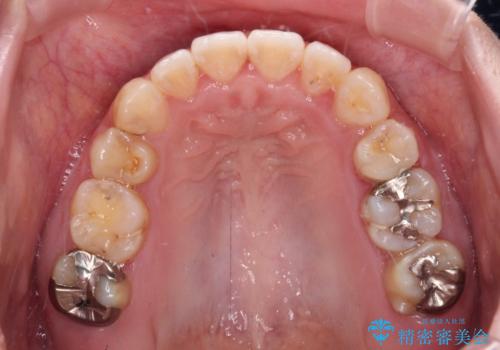

- 左上の八重歯と前歯のデコボコを気にして来院された患者様です。

下顎が左側にズレており、下顎前歯は1歯欠損していたため、左上小臼歯1本を抜歯し、ワイヤー装置にて矯正治療を行うこととしました。